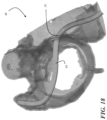

• step 108 comprises defining a plane that contains the ostium of the LAA 12.

• the plane being defined does not correspond to or contain what is conventionally considered by those of ordinary skill in the art to be the ostium of the LAA (referred to below as the "false ostium"), which is the opening of the LAA immediately adj acent the left atrium.

• the "ostium" of the LAA for purposes of this disclosure may comprise the portion or point of the LAA that has the greatest circumference/perimeter, that is distal of the conventional "ostium” of the LAA (i.e., further into the LAA and away from the left atrium than the conventional ostium), and that has a plane that is perpendicular to the centroid of the LAA.

• FIG. 7 illustrates a plane 42 containing the false ostium and a plane 44 containing the true ostium (plane 44 containing the true ostium is also shown in FIG. 6 ).

• a representation of the defined plane 44 may be displayed on the depiction 40 for the user to view, as shown in FIGS. 6 and 7 .